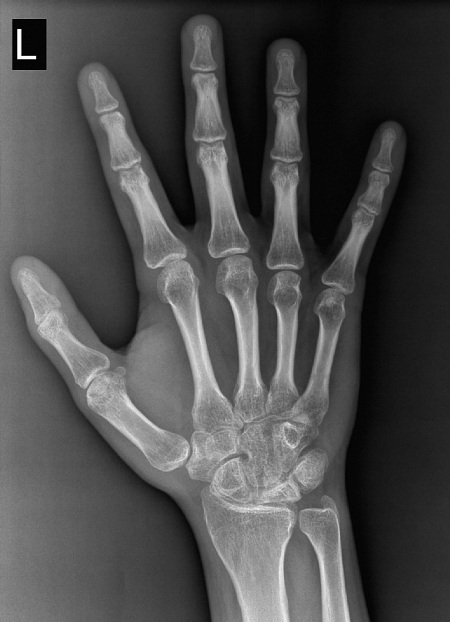

В клинику №1 Витерра Беляево к врачу - рентгенологу обратился пациент Л. 20 лет, с жалобами на ограничение подвижности и ноющие боли в левом лучезапястном суставе. В анамнезе — травма (перелом полулунной кости) и оперативное лечение (МОС) в 2017 году.

Пациенту была выполнена рентгенография лучезапястного сустава в 2-х проекциях.

Определяется деформация, уплощение и неравномерное склерозирование полулунной кости запястья, менее выраженные изменения определяются и в ладьевидной кости. Рентгенологические признаки локального остеопороза и проявлений артроза лучезапястного сустава.

Учитывая анамнез, клинику и достаточно типичную рентгенологическую картину, можно с большей долей вероятности предположить течение болезни Кинбека-Прейзера - состояние после асептического некроза ладьевидной и полулунной костей запястья.

После полученной травмы и оперативного вмешательства, а также в связи с длительной иммобилизацией сустава, было нарушено кровоснабжение данной области, что и привело к данным и, к сожалению, уже выраженным изменениям. Безусловно, выявление этой патологии на более ранней стадии с помощью рентгенологического, а также МРТ исследований, и своевременное начало консервативной терапии дало бы лучший результат, возможность избежать хирургического лечения и улучшение качества жизни. Берегите себя и своих близких!